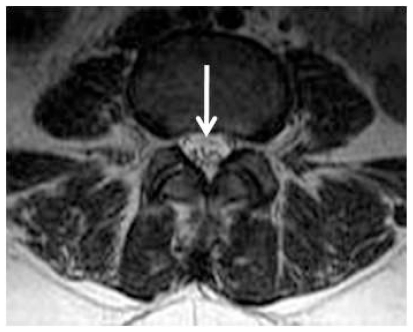

Figure 7.

39 year-old female with Guillain-Barré syndrome secondary to systemic lupus erythematosus. Contrast – enhanced axial T1-weighted MR imaging shows marked enhancement of the nerve roots in the conus medullaris and cauda equina (arrows).